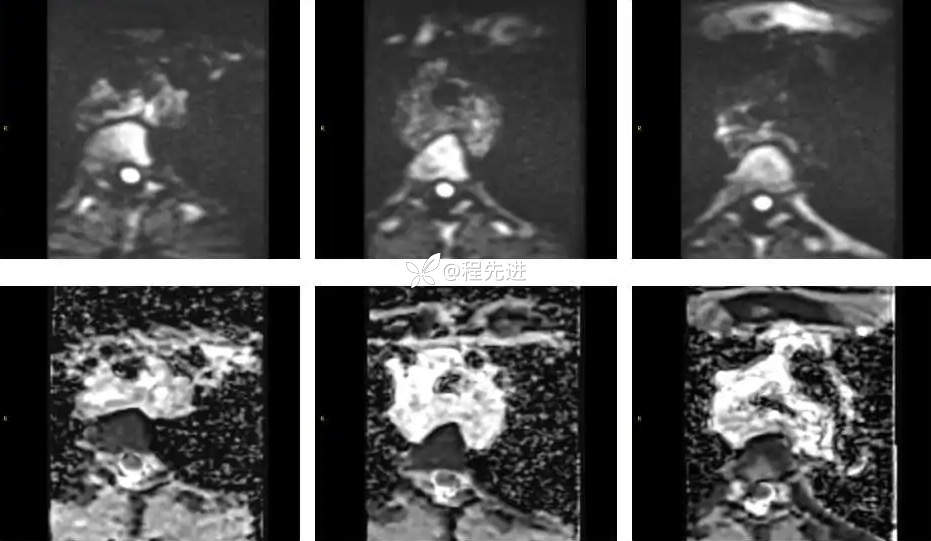

DWI、ADC: